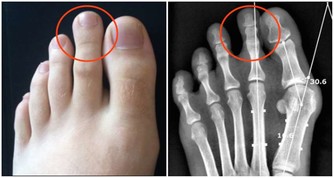

1、皮膚症狀:比如莫名的瘙癢、斑塊、疹子(不同於濕毒濕氣重等引起的瘙癢、濕疹)等,一些人還會出現指甲顏色、紋路的變異(要和灰指甲區分開來)。